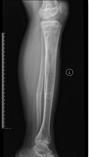

儿童陈旧性孟氏骨折

术后肘关节侧位片

术后1个月肘关节侧位片

儿童陈旧性孟氏骨折,术前桡骨小头陈旧性脱位,经截骨矫形治疗后1个月,桡骨小头已复位,患儿肘关节屈伸功能(1-2图),前臂旋转功能(3-4图)正常